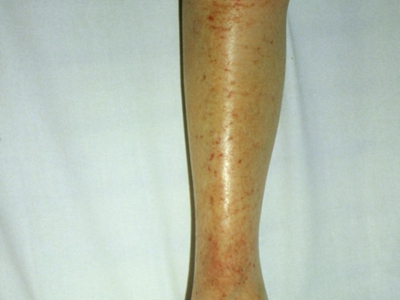

儿童期特应性皮炎发生于2岁以上的儿童,绝大多数由婴儿特应性皮炎延续发病,也有少部分儿童是在本期初发,多有丘疹、糜烂、苔藓样变等皮损表现。

儿童期特应性皮炎多呈现典型的湿疹改变,皮损渗出减少、干燥,以丘疹、糜烂和苔藓化为特点,特别好发于四肢、口周等处,最大特点是发生于两肘窝、两腘窝。皮损有轻度苔藓化,呈现糜烂面,少量渗出,自觉剧烈瘙痒。